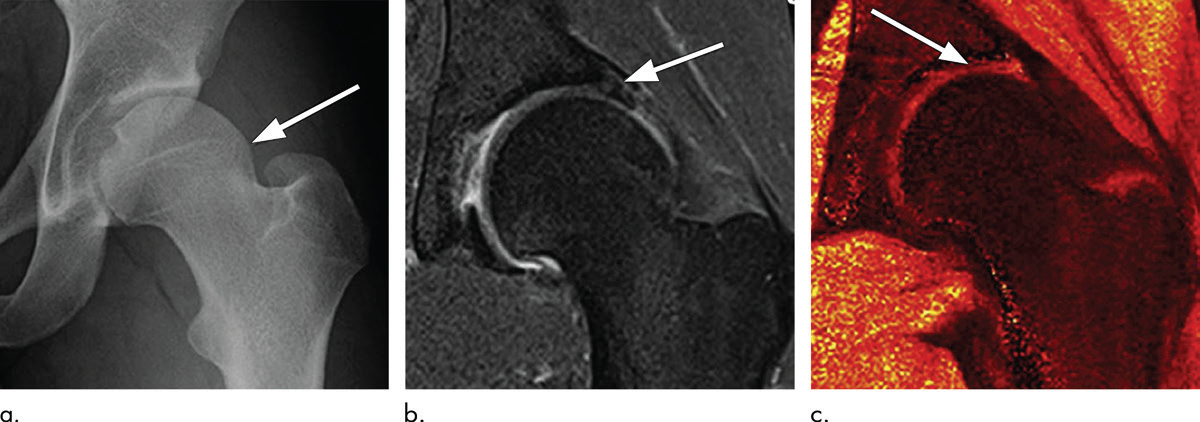

T1ρ成像:通过旋转坐标系下的T1弛豫时间评估蛋白多糖含量——蛋白多糖丢失时,T1ρ值升高,且基线T1ρ值可预测膝/髋OA进展(图6);

dGEMRIC:静脉注射含钆造影剂后,造影剂与软骨基质中带负电的蛋白多糖竞争结合位点,蛋白多糖丢失区域的造影剂摄取增加,T1值降低。该技术已用于发育性髋关节发育不良患者的术前评估,dGEMRIC指数异常的关节术后效果较差(图7)。

- MRI评估:采用专用线圈与高分辨率序列,可评估软骨损伤、盂唇病变、骨髓病变、滑膜炎,主流评分系统包括HOAMS、SHOMRI(评估14项关节特征);

- 成分MRI应用:dGEMRIC已用于股骨髋臼撞击症患者的术前评估,检测早期软骨退变;

- 放射学局限:X线难以显示髋臼顶软骨损伤,正常X线可能已存在MRI所示的结构异常。